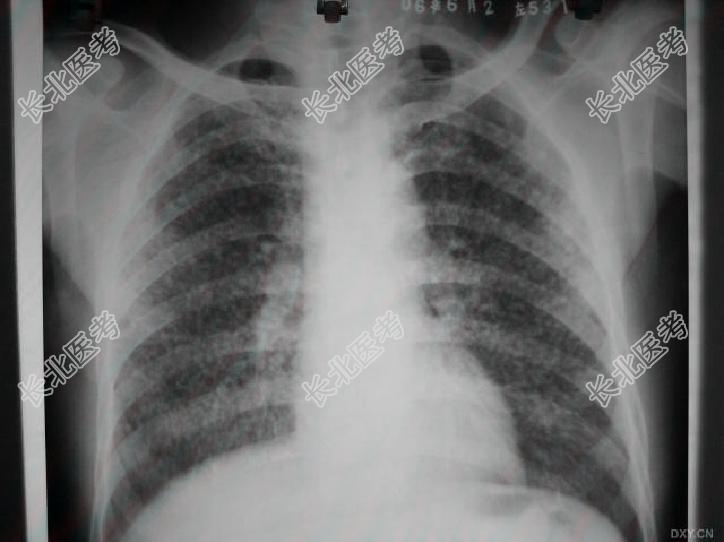

- 多项选择题3.提示:根据病史和X线影像。见下图。

,